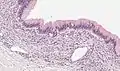

| Micrograph showing a mucinous cystadenoma of the ovary. H&E stain. | |

Mucinous cystadenoma is a benign cystic tumor lined by a mucinous epithelium. It is a type of cystic adenoma (cystadenoma).